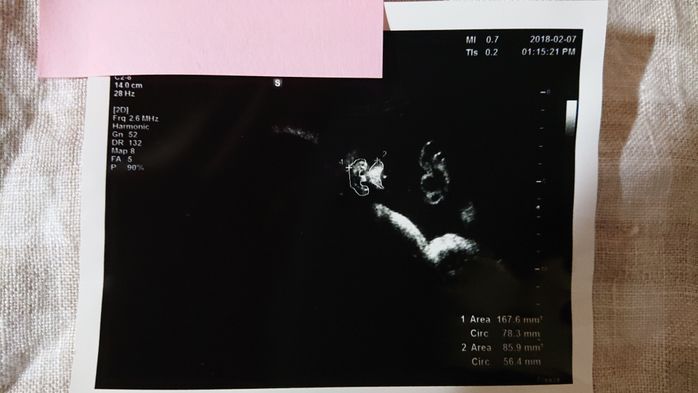

《妊娠8週目のエコー写真》

第1子を妊娠した時、妊娠検査薬に書かれた使用可能なタイミングを待てずに妊娠検査薬を試すと陽性反応が出て、すぐさま産婦人科を受診。すると、早すぎて胎嚢すら出来ていなかった…という経験から、第2子の時は妊娠検査薬で陽性の結果が出ても、病院へ行くのをしばし我慢していました。なので、本当にドキドキしながら待ちに待ったエコー写真です。今回は、赤ちゃんのお部屋である胎嚢も、赤ちゃんの姿もバッチリ確認できました。夫は長女と2学年差で第二子がほしいと希望していたのですが、長女と2学年差になるギリギリのタイミングでの妊娠判明だったので、「なんとかセーフ」とホッとしました。